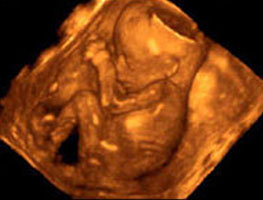

В 12 там ещё смотреть не чего ))) А в 30 уже совсем большой.. По этому в 20 самый оптимальный вариант, который помещаеся в экран, вот вам для примера фото с 3D узи в 20 неделек

11.03.2012